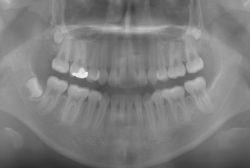

「乳歯が生え替わらない」という主訴で来院したケースです。 診断の結果、「左上永久犬歯が第一小臼歯後方上部に埋伏しているため、左上乳犬歯が晩期残存している症例」と判明しました。

このような症状の場合は、手術で埋伏している永久歯に金具を取り付け、矯正装置で牽引する必要があります。同時に凸凹の解消と前突した前歯を内側に入れるために上下左右の小臼歯を抜歯させて頂くことといたしました。

この方の場合は、マルチブラケット装置にて治療を開始し、治療期間2年3ヶ月で終了しました。犬歯の牽引距離が非常に大きかったため当院の平均治療期間よりも大幅に期間がかかりましたが、埋伏犬歯を完全に正しい位置まで誘導することができました。同時に 前歯の前突と配列の凸凹も解消しました。

このような症例は、成人してしまうと埋伏歯の反応性が悪く、あまりにも動きが悪い場合は牽引をあきらめて抜歯する場合もあります。歯科医院の検診で親知らず以外の埋伏歯を指摘された場合は、できるだけ早く矯正専門医に御相談下さい。